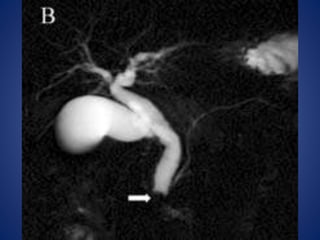

2. ANEURISMA DE AORTA ABDOMINAL

5. Aneurisma disecante de aorta abdominal